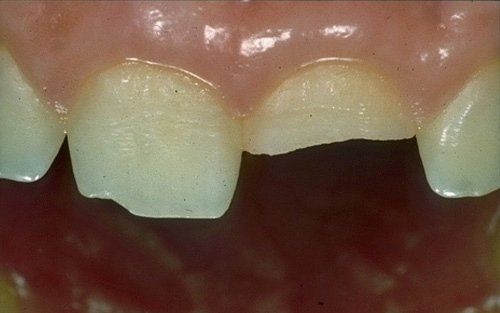

I denti da latte traumatizzati più spesso vanno incontro a necrosi con conseguente cambiamento di colore, divenendo grigiastri, segno della morte delle cellule della polpa dentaria. In altre occasioni, il dente può fratturarsi in maniera più o meno ampia: se il frammento viene ritrovato, potrà essere re-incollato in maniera invisibile, oppure verrà ricostruito con i materiali compositi.